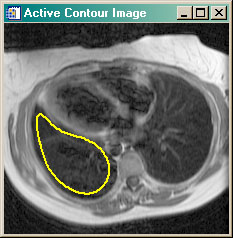

- cgSNAKE Applies active contouring Gradient Vector Flow "snake" contour algorithm to 2D dataset.

cgSNAKE | |

This program is similar to the

ActiveContour program in that it implements the Gradient Vector Flow

active contouring method of Xu and Prince. It differs in that it does so without

requiring an interactive GUI. In other words, the GVF algorithm can be applied to

a 2D dataset as a function, in the manner of other image processing functions.

The program requires that the GVF_Snake program be purchased from the Coyote Store. You can read more about active contouring in the article Active Contouring (Snakes) in IDL. |